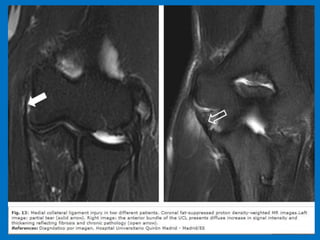

Medial epicondylitis (Golfer's elbow). Coronal fat-suppressed proton

density-weighted MR images . On the left image, a partial tear of

the common flexor tendon (white arrow) is observed. On the right

image, the common flexor tendon origin is usually thickened and

shows increased signal intensity (yellow arrow).Note the presence of

subtle bone marrow edema in the medial epicondyle (blue arrow).